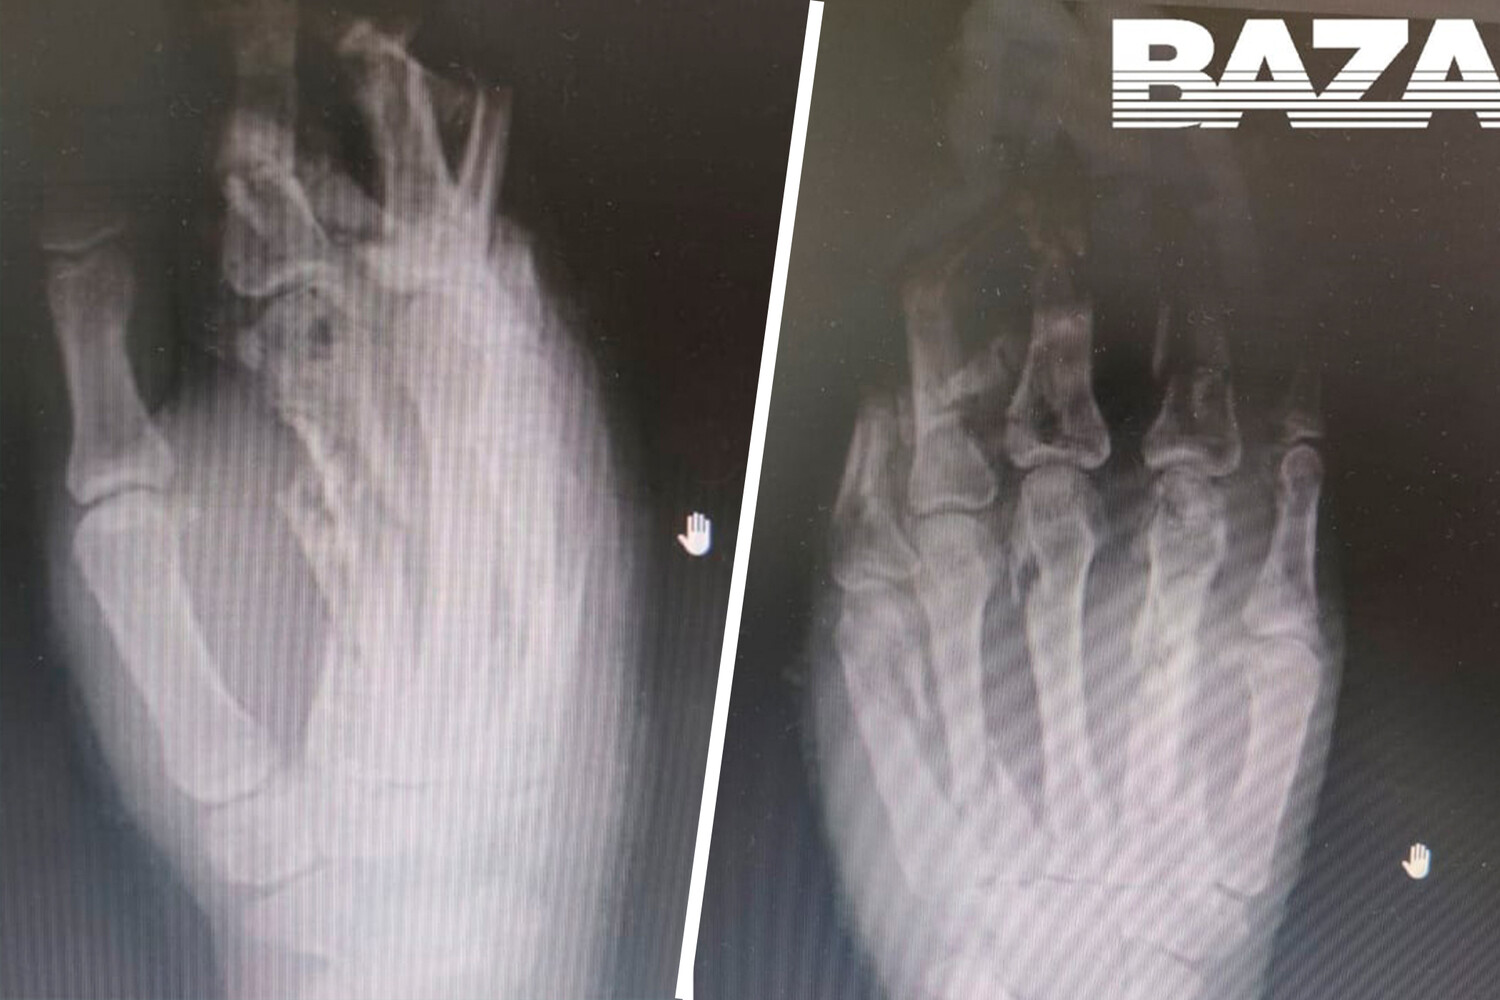

В Подмосковье врачи спасли кисть девушке, рука которой застряла в электрической мясорубке: почти все ее пальцы сломаны и частично перемолоты, сообщается в Telegram-канале «Baza».

Врачи осмотрели пациентку и провели необходимые процедуры, оказалось, что почти все пальцы ее левой руки сломаны и частично перемолоты. Травматологи и анестезиологи три часа проводили необходимые медицинские вмешательства, в результате которых удалось спасти не только кисть девушки, но и все ее пальцы.

Сейчас поврежденная конечность полностью обработана. Для ее восстановления врачи установили на руке специальный аппарат, который поможет облегчить этот процесс.